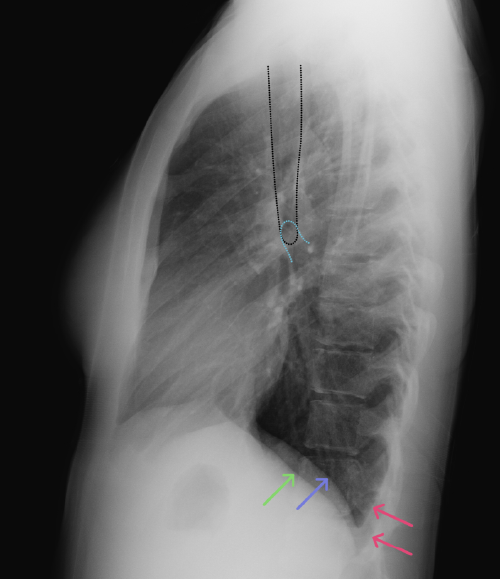

Chest

Chest

Chest radiograph & CT anatomy

Chest

Chest

Chest radiograph & CT anatomy